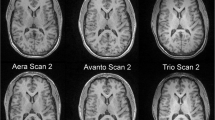

For clinical purposes and research projects in neurological disease, it is of interest to evaluate the performance and comparability of available sequences and software packages for brain volume assessment to determine whether they provide equivalent results. This study compares cross-sectional brain volume values derived from images obtained with MP-RAGE or MP2RAGE sequences, using SIENA/X, SPM, or MorphoBox.

MP-RAGE and MP2RAGE T1-weighted images were obtained from 24 healthy volunteers. Back-to-back scans were performed in 12 of them. Brain volumes, coefficients of variation, and concordance coefficients were determined.

Significant differences were found for most brain volumes derived from MP-RAGE and MP2RAGE images. MP2RAGE-derived measures showed a non-significant trend to larger coefficients of variation. There were statistical differences between brain volumes determined with the three software packages, whereas coefficients of variation were comparable for most brain volumes. Correlation and concordance values were lower for CSF and brain parenchyma fraction measures.

The results obtained advise caution when comparing brain volumes obtained by different sequences and software packages. Of note, for most brain volume measures, the MP2RAGE and MorphoBox coefficients of variation were similar to those obtained with MP-RAGE, SIENA/X or SPM, accepted tools for clinical research.